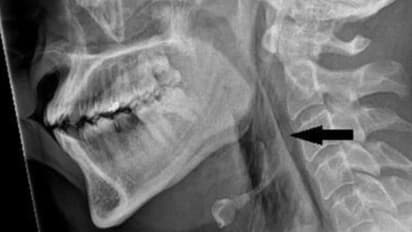

Medical examinations, including X-rays and CT scans, revealed extensive damage caused by the sudden and forceful suppression of the sneeze. Surgical emphysema, a condition where air accumulates in deeper tissue layers, was evident, along with a tear detected between the third and fourth vertebrae in the neck. Additionally, air had collected in the area between the lungs and chest.